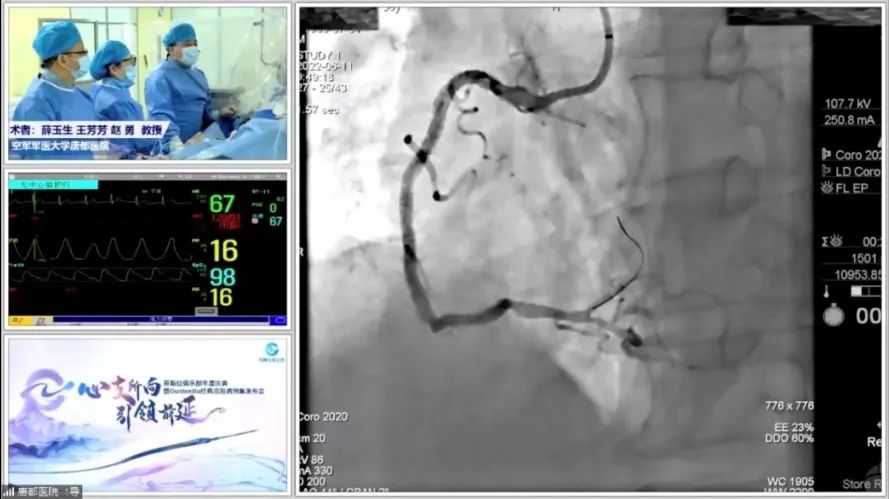

钙世英雄 全面出击

旋磨是应对重度钙化的利器

▼▼▼

下午场的学术活动聚焦PCI领域的坚硬堡垒——钙化病变,由西安交通大学第一附属医院雷新军教授、空军军医大学唐都医院薛玉生教授、郭万刚教授、陕西省人民医院姚晓伟教授共同主持,邀请陕西省人民医院张勇教授、西安市人民医院程康教授、空军军医大学唐都医院牛晓琳教授作为讨论嘉宾。

图片

首先,陕西省人民医院梁磊教授结合个人心得体会对最新冠脉钙化病变诊治专家共识进行了解读。他提到,与2014版钙化专家共识相比,2021版钙化专家共识结合近年来国内外专家共识对钙化病变的治疗策略进行了更新,同时旋磨的特定适应证、旋磨终点判断等也进行了新增,而且新增了钙化病变的预处理方法、引入了OCT指导下的钙化积分系统等。

空军军医大学西京医院王琼教授摒弃策略和方法,介绍了钙化病变的影像学诊断方法,系统详尽的从冠脉CT、造影、IVUS等影像学技术来评估钙化的特征。王琼教授最后表示,影像学的进步,可以帮助医生对钙化进行多维度、多时段、不同情况的深入了解,更好地采取相应精准的治疗策略。

唐都医院马文帅教授复盘了一例IVUS指导下钙化病变精准治疗的病例。并强调在手术时,要尽早进行旋磨,而IVUS在指导钙化病变中有非常重要的作用,可帮助医生了解和应对钙化病变。

李妍教授也介绍了处理钙化病变的新技术进展情况,谈到处理钙化病例需要多项技术的联合应用,方能应对复杂严重钙化病变。

李成祥教授作为国内冠脉钙化病变治疗领域先行者,介绍了旋磨的应用场景,从冠脉钙化病变发生率、旋磨发展情况和旋磨临床研究及专家共识等方面回顾了旋磨钙化病变的现状和进展,非常有意义。并强调,对于严重钙化病变,旋磨是唯一有效的利器;对于传统器械无法提供血管通路时,旋磨是一个必不可少的工具。相信未来,随着PCI的不断增长,中国将是旋磨大国,旋磨或将焕发新一春!

陕西省人民医院梁栋教授作为一名初学者,列举了之前做过的一例严重钙化病例中所遇到的困难,并分享了自己的心得体会。他认为,Guidezilla基于其强支撑的特性,可以开发出丰富的应用场景,此次参考磨头嵌顿的使用方法解决钙化病变切割球囊嵌顿问题,充分证实了Guidezilla使用的多种用途。

学术汇报期间,唐都医院李妍教授团队,王翅遥教授、马文帅教授还演示了两例非常复杂的冠状动脉粥样硬化性心脏病患者使用Guidezilla开展旋磨的精彩病例演示,提示大家要重视冠脉病变和钙化病变影像学的检查,有非常重要的教育意义。